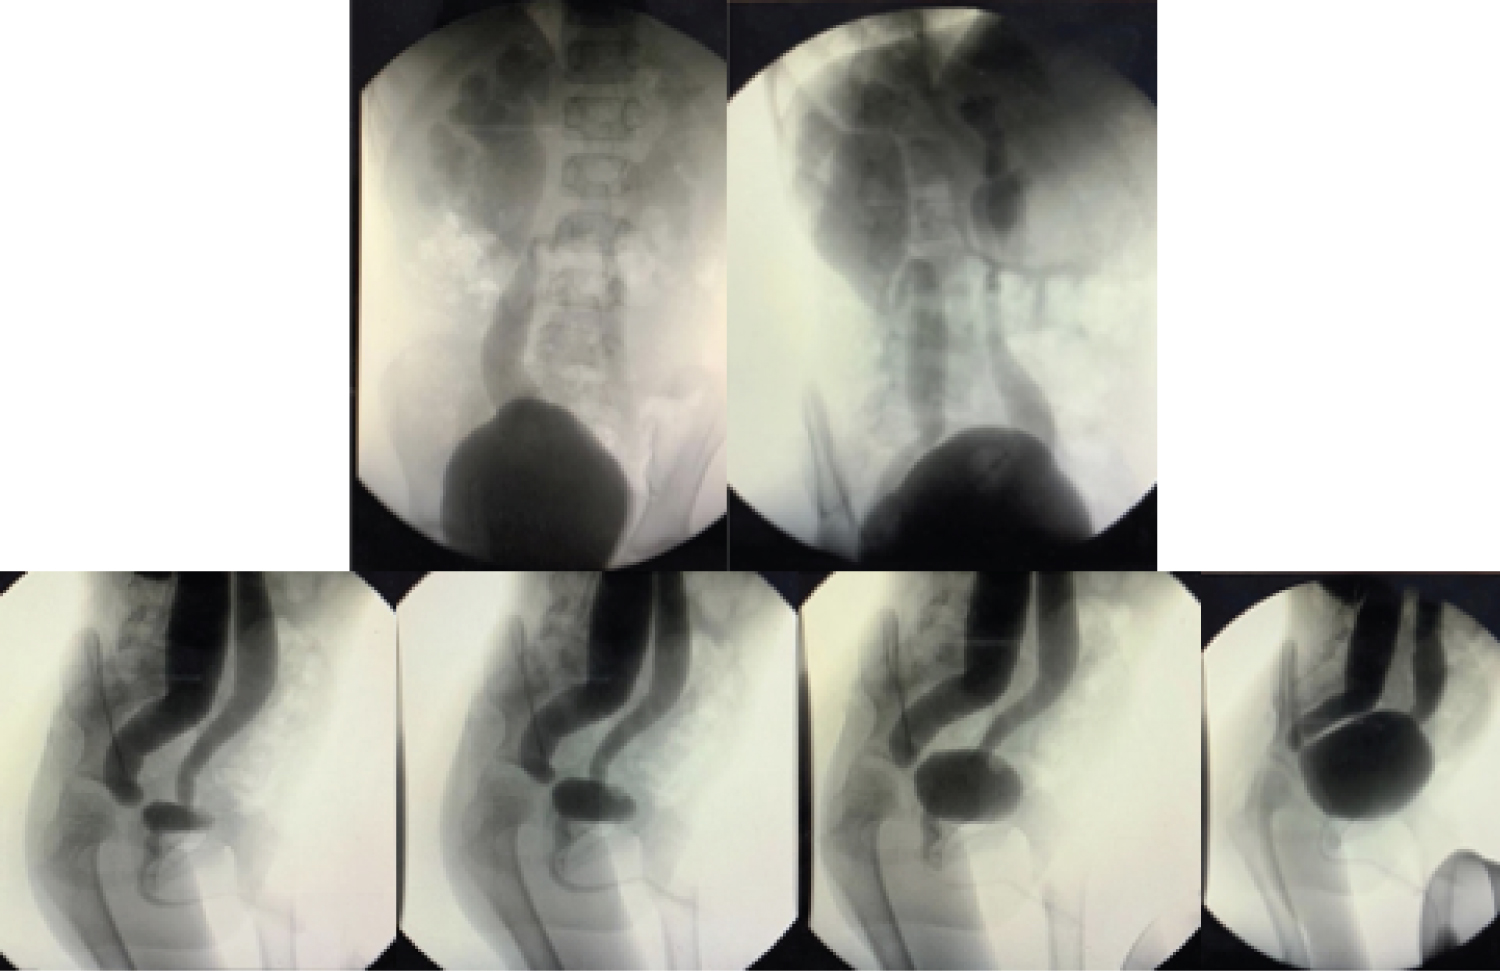

Figure 2: Voiding cystourethrography demonstrated bilateral ureteral dilation and tortuosity with right predominance, the right kidney shows dilation of pelvis and calyces. View Figure 2

With these ultrasonographic findings, a voiding cystourethrography (VCUG) was performed, in which ureteric and pelvicalyceal dilation was evident and the diagnosis of Grade V VUR in the right kidney and Grade IV VUR in the left kidney were confirmed (Figure 2). The patient was eventually referred to a pediatric urologist for further surgical management.